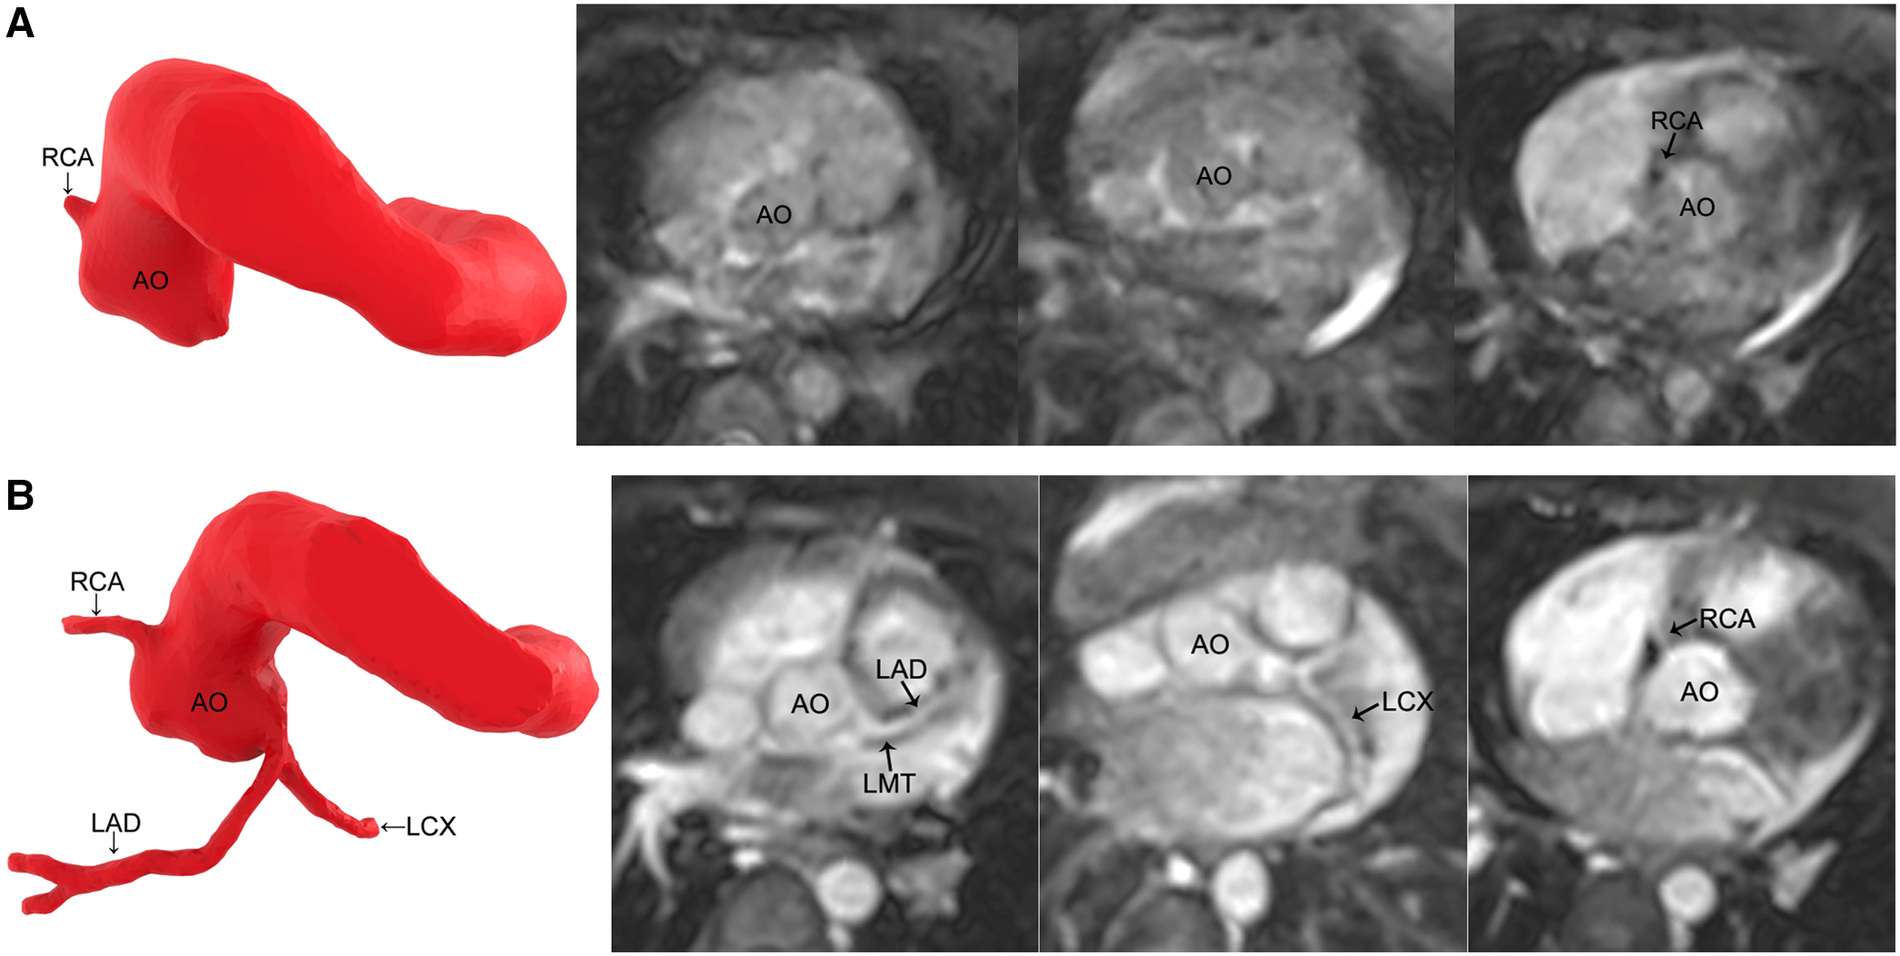

Figure 1

MR coronary angiography in a 7-month-old boy. (A) Noncontrast-enhanced MR coronary angiography only detects the origin of the RCA. (B) Contrast-enhanced MR coronary angiography images reveal all the coronary arteries. The image quality improves significantly. RCA, right coronary artery; AO, aorta; LMT, left main trunk; LAD, left anterior descending coronary artery; LCX, left circumflex coronary artery.